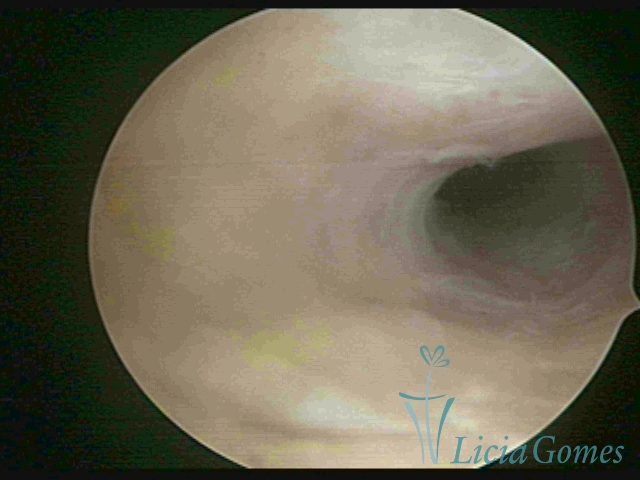

First part or proximal section or lower section:

During the proliferative phase, a light, crystalline mucus with a low adherence to the scope is found. The crypts and buds are a little swelled and vascularized, microvesicular, resembling grape clusters.